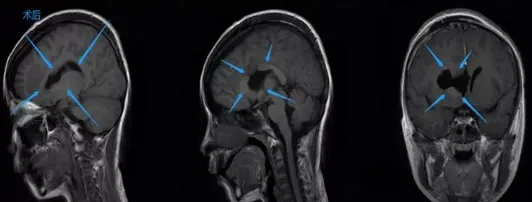

手术那天天气不错,我感觉整个人也被照亮了,女儿手术后被推入ICU观察,巴教授走出手术室告诉我,手术十分成功,肿瘤几乎全切,那一刻我激动地语无伦次,只能一遍遍说谢谢。

2天后,女儿从ICU转出,没有任何神经功能受损,短短7天时间,她就能下床自己走路,之前听说的术后可能出现的严重并发症,一个都没有发生,女儿没多久就又变得活泼起来,与生病之前一样。